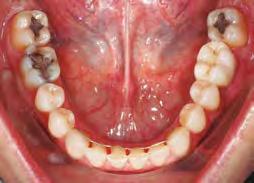

–Corticotomías y Ortodoncia. Ampliando límites del movimiento dental, por la Dra. Aranzazu Senosiain y cols. [50]

–Tratamiento de un caso de Ortodoncia y Cirugía Ortognática con placas preformadas y tecnología 3D, por la Dra. Elena Bonilla Morente y cols. [62]

–Uso del anclaje esqueletal como alternativa eficiente en el manejo ortopédico de clases III por deficiencia de maxilar superior, por el Dr. Carlos Becerra y cols. [74]

–MARPE, una alternativa a la disyunción en el paciente adulto, por el Dr. Enrique Solano y cols. [88]